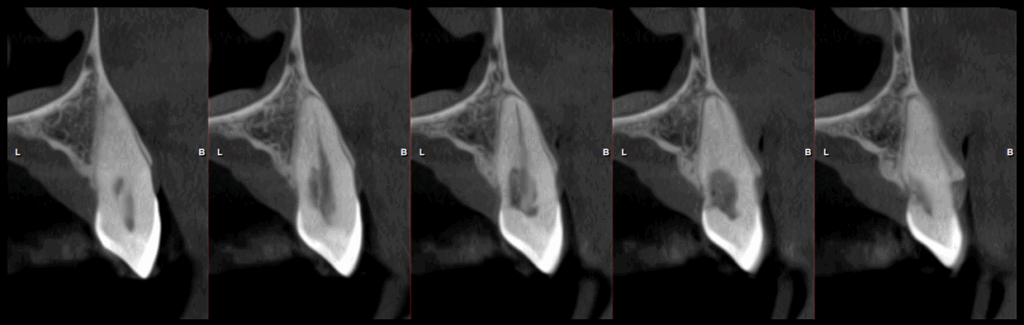

En la tomografía computarizada de haz cónico se identifica en la pieza 23 una imagen isodensa que compromete las paredes radiculares mesial, distal y palatina a nivel del tercio cervical, en estrecha proximidad con el conducto radicular. Asimismo, se observa un ensanchamiento del espacio del ligamento periodontal adyacente.

CORTES TANGENCIALES